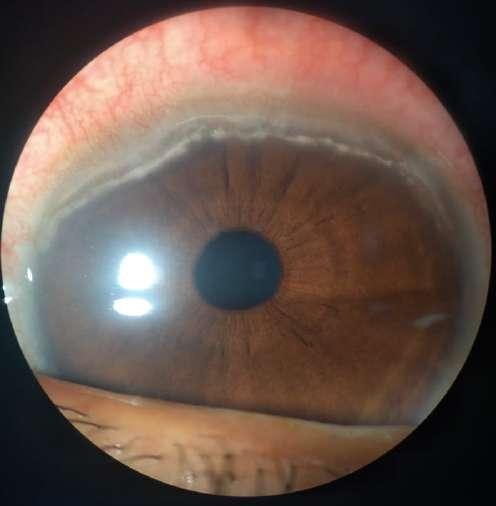

Imágenes aportadas por Dr. Cristian Sánchez

ü La degeneración macular relacionada a la edad es la causa más frecuente de pérdida de visión irreversible en personas mayores de 60 años

ü La patogenia es multifactorial, en que además del envejecimiento (principal factor de riesgo) los factores de riesgo genéticos y ambientales (Tabaquismo, obesidad abdominal) juegan un rol determinante

ü Su primera manifestación son las drusas sin embargo el proceso puede evolucionar a la forma seca o húmeda

ü La forma húmeda se caracteriza por la presencia de membrana neovascular coroidea que crece bajo el epitelio pigmentario y luego bajo la retina. Estos vasos de neoformación se originan en la coriocapilar, proliferan y penetran al espacio subepitelial a través de una ruptura de la membrana de Bruch

ü El desprendimiento de epitelio pigmentario puede preceder la neovascularización coroidea, y en ese caso su contenido es seroso, cuando se asocia a neovascularización coroidea su contenido es fibrovascular

ü Al examen oftalmoscópico, en caso de tener una membrana neovascular, se detecta un solevantamiento retinal, habitualmente redondeado y generalmente rodeado de un halo de sangre subretinal. El solevantamiento se debe a la presencia de líquido o edema retinal. La membrana neovascular puede ser extrafoveal, alejada del centro, pero en la mayoría de los casos es subfoveal

ü Una complicación inusual es la hemorragia subretinal masiva, lo que en algunos pacientes se asocia a terapia anticoagulante

ü Angiografía con fluoresceína en la membrana MNVC Tipo Ia (DEP fibrovascular): se caracteriza por presentar área hiperfluorescente irregular visible desde un tiempo arteriovenoso precoz que incrementa la fluoresceina en tiempos tardíos con poca o nula difusión

2.G. MEMBRANA NEOVASCULAR COROIDEA (MNVC)

Clement F . “Angiografía”. Diagnóstico por la imagen en la retina, Sociedad Española de Retina y Vítreo, editado por Ignasi Jügens, Elservier, 2014, pp 41-66 Juan Verdaguer, T. (2010). Degeneración macular relacionada a la edad. Revista Médica Clínica Las Condes, 21(6), 949–955. doi:10.1016/s0716-8640(10)70620-9

A B